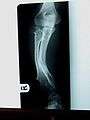

Hereditary multiple exostoses (HME or MHE), also known as diaphyseal aclasis, is a rare medical condition in which multiple bony spurs or lumps (also known as exostoses, or osteochondromas) develop on the bones of a child. HME is synonymous with multiple hereditary exostoses and multiple osteochondromatosis, which is the preferred term used by the World Health Organization.

It is characterized by the growth of cartilage-capped benign bone tumours around areas of active bone growth, particularly the metaphysis of the long bones. Typically five or six exostoses are found in upper and lower limbs. Most common locations are:[1]

HME can lead to the shortening and bowing of bones; affected individuals often have a short stature. Depending on their location the exostoses can cause the following problems: pain or numbness from nerve compression, vascular compromise, inequality of limb length, irritation of tendon and muscle, Madelung's deformity[2] as well as a limited range of motion at the joints upon which they encroach. A person with HME has an increased risk of developing a rare form of bone cancer called chondrosarcoma as an adult.[2] Problems may be had in later life and these could include weak bones and nerve damage.[3][4][5] The reported rate of transformation ranges from as low as 0.57%[6] to as high as 8.3% of people with HME.[7]